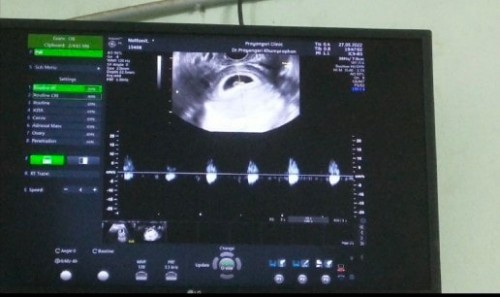

หัวใจเด็กเต้นช้า

คุณหมอบอกว่าอายุครรภ์ประมาณ 6w หัวใจน้องเต้นช้าไปหน่อย คุณหมอนัดอีก 2 w ไปพบคุณหมอใหม่ค่ะ มีแม่ๆบ้านไหนเคยมีประสบการณ์หัวใจน้องเต้นค่อนข้างช้าไหมคะ